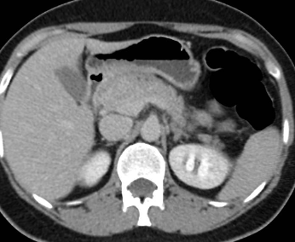

Paciente masculino de 35 años de edad, con antecedentes de tabaquismo, etilismo, consumo de sustancias psicoactivas. Ingresa al hospital de Sanatorio Franchin el 24 de mayo de 2024, donde se constata hipoglucemia severa con buena respuesta al glucosado hipertónico endovenoso. Al examen físico con la típica tríada de Whipple, dado por síntomas neuroglucopénicos de alteración del estado de conciencia, glucemia de 25 mg/dl y alivio sintomático después de la administración de glucosa. El paciente recupera el estado de conciencia y refiere dolor abdominal a nivel de epigastrio, por lo que se le realiza ecografía abdominal, donde se evidencia lesión nodular hipoecogénica en cuerpo del páncreas. Por esta razón se pasa al paciente a tomografía, donde se constata una formación nodular a nivel del cuerpo del páncreas, que presenta un ávido realce en fase arterial con homogeneización de la lesión en tiempo tardío.

Una vez que tengamos una fuerte sospecha diagnóstica basada en la clínica y el laboratorio bioquímico viene la localización del tumor, que se puede realizar a través de métodos no invasivos, como la ecografía, que como método de abordaje inicial no está mal para una primera exploración, pero debemos conocer que su sensibilidad es muy baja, del 9%. Pero como un estudio no invasivo, rápido, relativamente económico, y si está disponible en nuestro servicio, se puede utilizar. Los insulinomas se pueden observar por este método como una imagen nodular hipoecogénica que puede mostrar ante la presencia de Doppler color un patrón periférico o centrípeto, porque recordemos que estos son tumores hipervasculares, lo que significa que tienen una alta densidad de vasos sanguíneos.

Ahora bien, como se mencionaba al principio, el estudio ecográfico es de muy baja sensibilidad y se identifique o no la lesión por este estudio, nuestro siguiente paso en el algoritmo diagnóstico de esta lesión es la tomografía. Esta es la prueba no invasiva inicial, con una sensibilidad del 63% al 83%, y detecta del 70% al 80% de los tumores. Esta debe realizarse como un estudio trifásico: fase arterial temprana a los 30 segundos, fase venosa a los 70 segundos, fase tardía de 3 a 5 minutos. La característica de estos tumores por tomografía es que se presentan como una masa sólida que tiene un ávido realce en la fase arterial, cuyo realce se mantiene y se observa más tenue en la fase venosa y en los tiempos tardíos la lesión se homogeniza.

Para mi caso, y dando una visión general de los métodos de imagen no invasivos en esta revisión retrospectiva, solo a uno de los pacientes se le detectó la lesión por ecografía, donde se visualizó una lesión nodular hipoecogénica en el cuerpo del páncreas. A los demás pacientes se les detectó la lesión por tomografía en estudio trifásico, donde resaltan las características ya descritas por la literatura de lesiones hipervasculares con intenso realce en fase arterial, localizadas en diferentes partes del páncreas, como cabeza, cuerpo y cola.